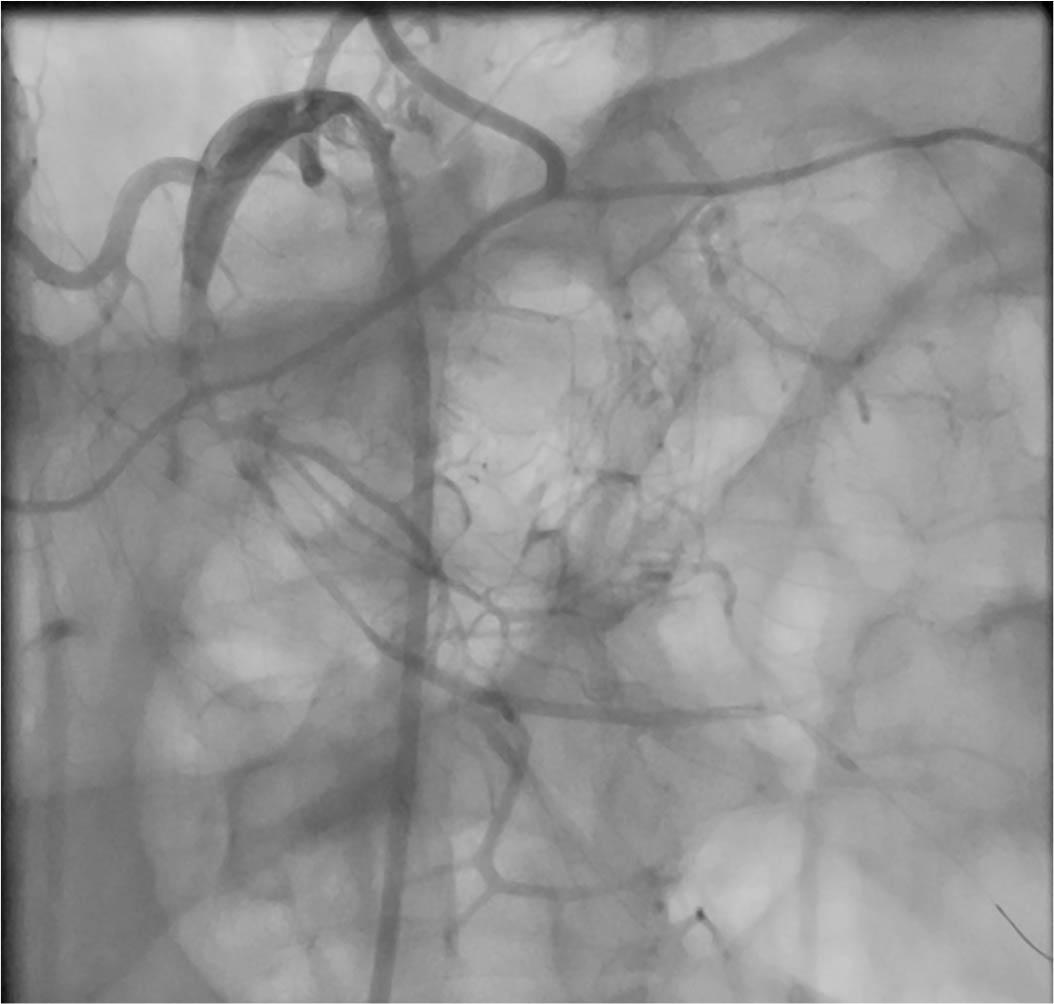

Figure 4